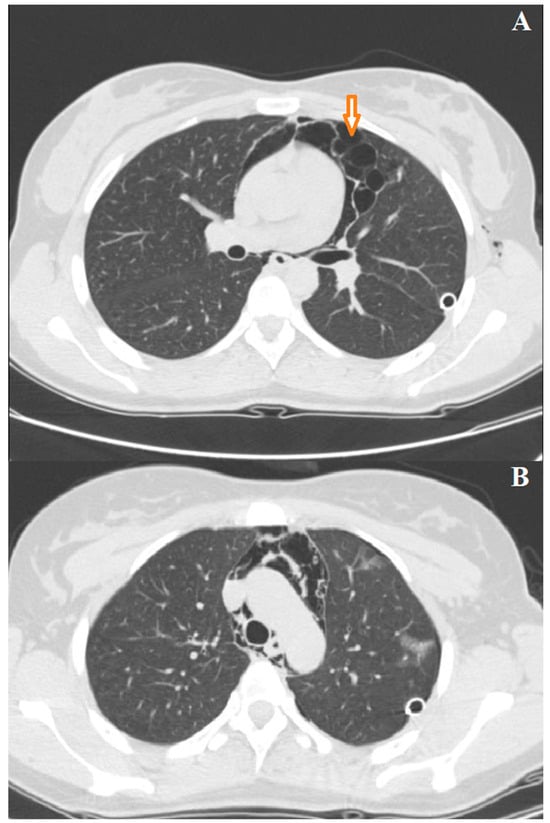

3.3. Case 3